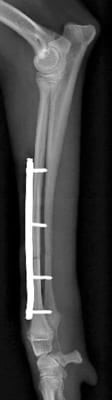

右前肢

右前肢はLag Screw固定の併用が可能だったので1期癒合

右前肢は骨片間圧迫を加えているため、骨折端同士が直接癒合します。

そのため仮骨形成が少なく、早期に癒合します。

術後19日 右前肢は治療終了です。